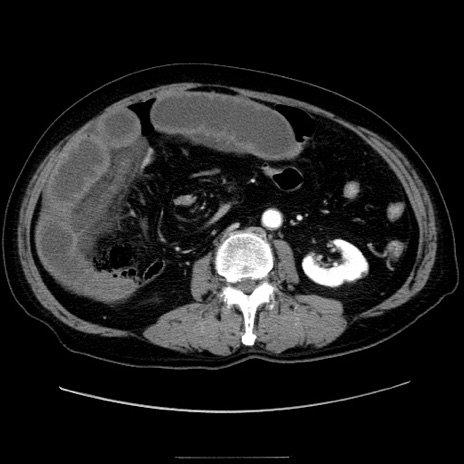

症例30(横断像)

【症例】80歳代男性

【主訴】臍周囲痛

【現病歴】約6時間前から臍下部痛が出現。次第に腹部膨隆・背部痛も生じてきたため来院。背部痛の場所は変化しない。

【既往歴】腎盂腎炎

【身体所見】意識清明、BT 36.3℃、BP  131/87mmHg、P 87bpm、SpO2 100%(RA)、臍周囲自発痛・圧痛あり、反跳痛なし、自発痛部位に一致して板状硬あり、腹部膨隆、腸雑音減弱、CVA tenderness両側陰性。

【データ】WBC 19600、CRP 0.33